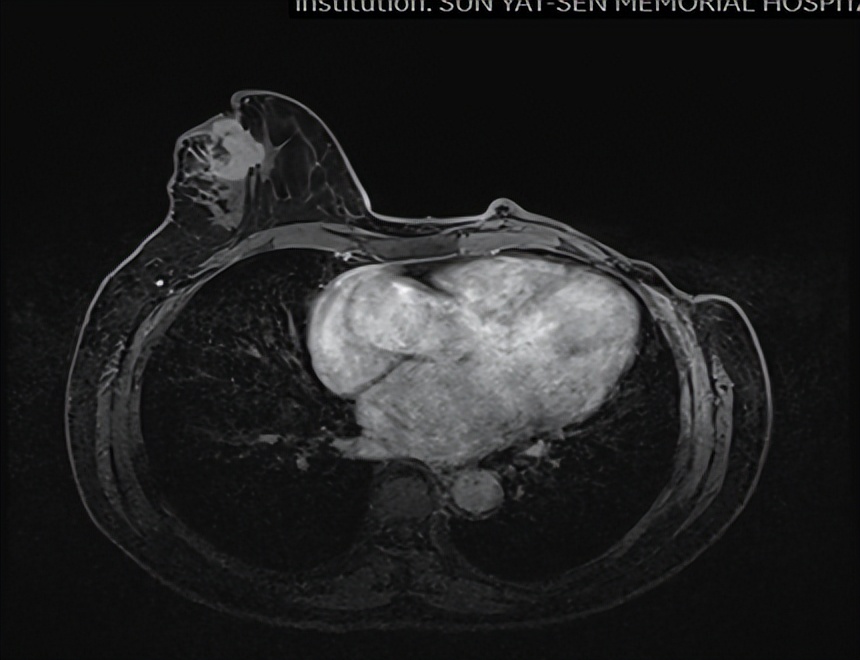

乳腺MR

右侧乳头后侧中部多个异常信号结节(较大者23*15mm),符合乳腺癌,BIRADS:5类。右侧腋下肿大淋巴结,考虑转移。

1.右乳外上象限乳腺癌病灶(22*16mm),对比2023-04-14 CT(26*24mm)较前缩小,FDG代谢活跃。右侧腋窝小淋巴结(5mm),较前稍缩小,代谢不活跃。右侧锁骨上区、上纵隔淋巴结转移瘤(24*18mm),现大小同前相仿,代谢活跃(SUV:6.7)。